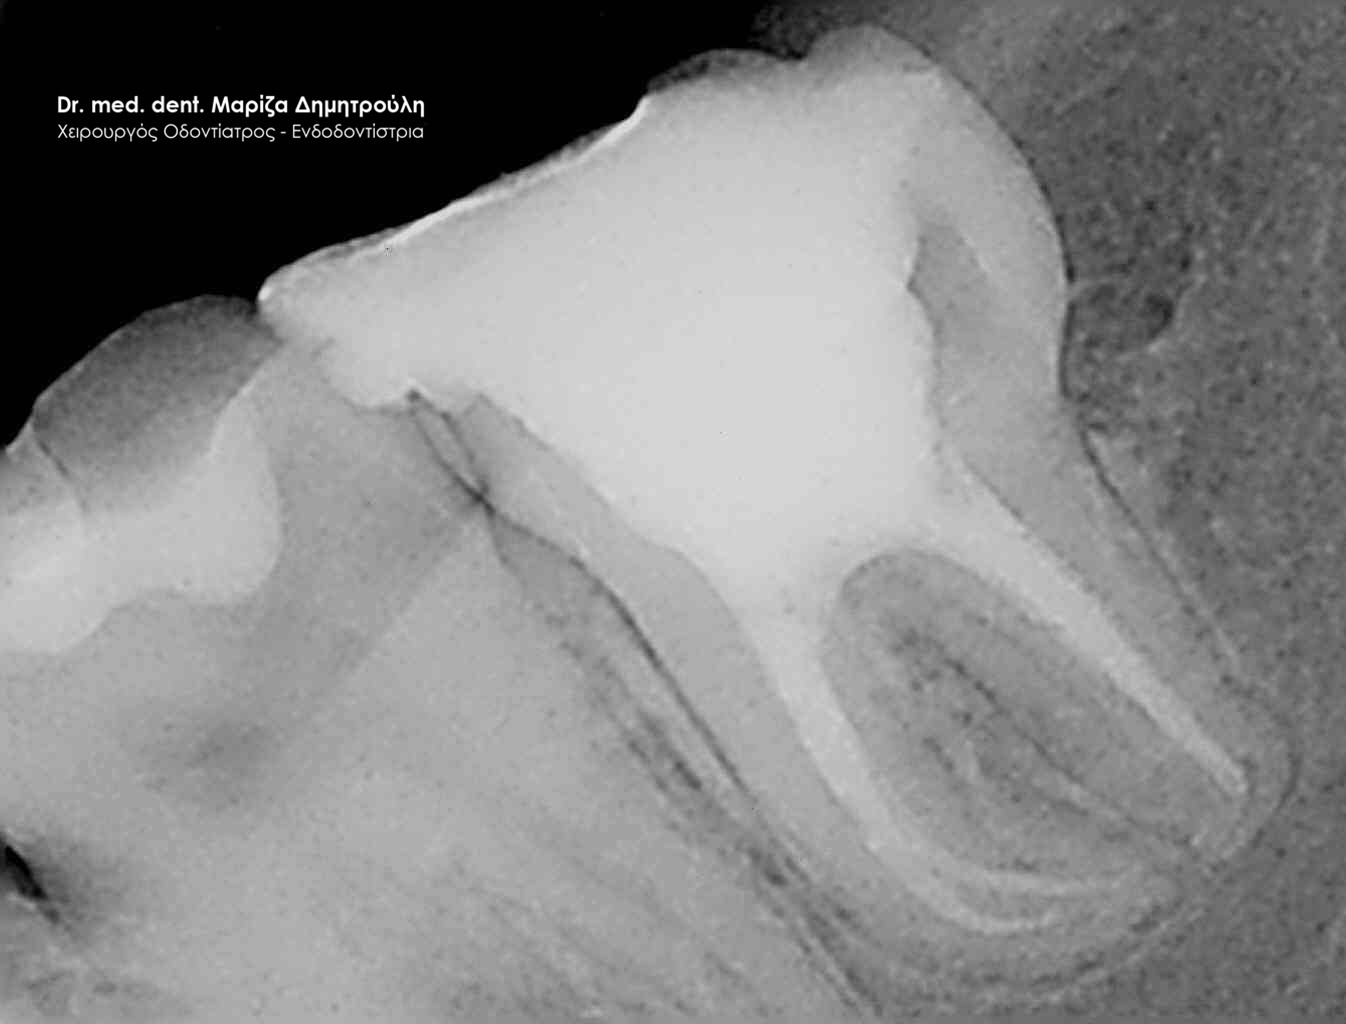

Η ασθενής περιγράφει έναν έντονο συνεχόμενο πόνο στη δεξιά πλευρά της άνω γνάθου που δεν την αφήνει τις τελευταίες μέρες μα εργαστεί. Μετά την κλινική και ακτινογραφική εξέταση της περιοχής διαπιστώθηκε οτι το υπαίτιο δόντι για την πρόκληση των έντονων συμπτωμάτων ήταν ο δεύτερος δεξιός άνω γομφίος, ο οποίος διέθετε ένα παλιό βαθύ σφράγισμα που πίεζε το νεύρο του δοντιού.

Μετά τη χορήγηση τοπικής αναισθησίας αφαιρέθηκε το παλιό σφράγισμα και εντοπίστηκαν οι ριζικοί σωλήνες του δοντιού (βλέπε φωτογραφία). Μετά την κατάλληλη επεξεργασία των ριζικών σωλήνων και εφόσον το δόντι ήταν ασυμπτωματικό η απονεύρωση ολοκληρώθηκε με την έμφραξη των ριζικών σωλήνων με ειδικό εμφρακτικό υλικό.

ΠΡΙΝ